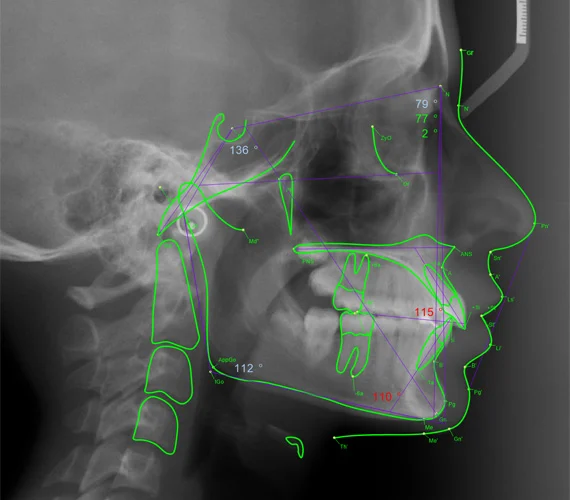

Cas 3 : Classe III Squelettique Légère

Données céphalométriques :

- SNA : 78° (légèrement diminué)

- SNB : 80° (légèrement augmenté)

- ANB : -2° (classe III squelettique)

- Convexité : -1 mm (profil concave)

- FMA : 26° (normal)

- Li/E : +2 mm (protrusion labiale inférieure)

Diagnostic : Classe III squelettique modérée par combinaison de rétromaxillie et légère prognathie mandibulaire.

Options thérapeutiques :

- Chez l’enfant jeune : masque de Delaire pour traction maxillaire antérieure

- Chez l’adolescent : camouflage orthodontique avec compensation dento-alvéolaire

- Chez l’adulte avec décalage sévère : chirurgie bimaxillaire